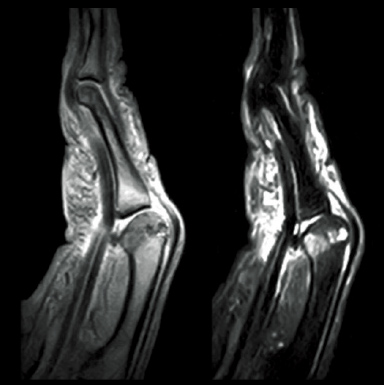

left:T2*WI right:STIR